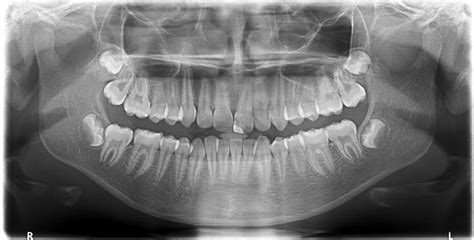

When you visit your dentist for a comprehensive oral health assessment, they may recommend a specialized imaging procedure to get a complete picture of your dental structures. This is where a dental panoramic X-ray, often referred to as an orthopantomogram (OPG), becomes an invaluable tool. Unlike traditional bitewing X-rays that focus on a few teeth at a time, this diagnostic technique captures a wide, sweeping view of your entire mouth, including the teeth, upper and lower jaws, jaw joints (TMJ), and surrounding structures, all on a single film or digital image.

A dental panoramic X-ray is a two-dimensional imaging technique that rotates around the patient’s head to produce a comprehensive image of the oral cavity. Because it captures so much information in one scan, it provides dentists with a broader diagnostic perspective than localized images. It is commonly used in various areas of dentistry, ranging from general checkups to specialized treatments like orthodontics and oral surgery.

- Comprehensive View: It captures the entire jaw, allowing the dentist to spot issues that might not be visible in standard, focused X-rays.

Dentists rely on dental panoramic X-ray imaging for a wide array of clinical evaluations. It serves as a foundational piece of data for treatment planning, especially for procedures that require a comprehensive understanding of the jaw anatomy.

| Orthodontic Assessment | Root positions, spacing issues, and unerupted teeth. |

| Wisdom Teeth Removal | Proximity of third molars to nerves and sinus cavities. |

| Periodontal Disease | Extent of bone loss around the teeth. |

| TMJ Evaluation | Joint structure and signs of jaw dysfunction. |